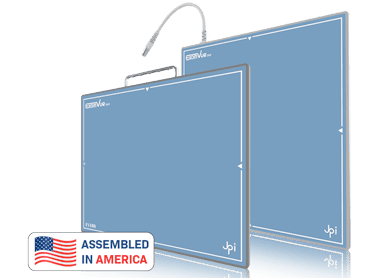

Diseñado para optimizar la captura de imágenes radiográficas con la más alta calidad y eficiencia

DRE DUO

Detector digital de rayos X portátil con doble panel para captura rápida y precisa de imágenes radiológicas.

Diseñado para optimizar la captura de imágenes radiográficas con la más alta calidad y eficiencia

La estructura optimizada de TruePortable™ no solo reduce significativamente el peso para una manipulación más cómoda durante periodos prolongados de trabajo

Protector para panel plano diseñado para resguardar el detector de golpes y derrames, garantizando su durabilidad y un rendimiento de imagen óptimo.